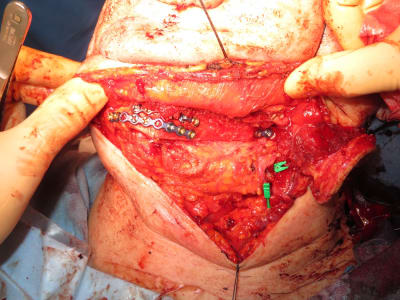

Protocole de modélisation 3D pour greffe de Fibula avec guide de coupe de péroné et d’ostéotomie mandibulaire.

Vous souhaitez découvrir les dispositifs de coupes sur mesure réalisés en acier chirurgical: [email protected]